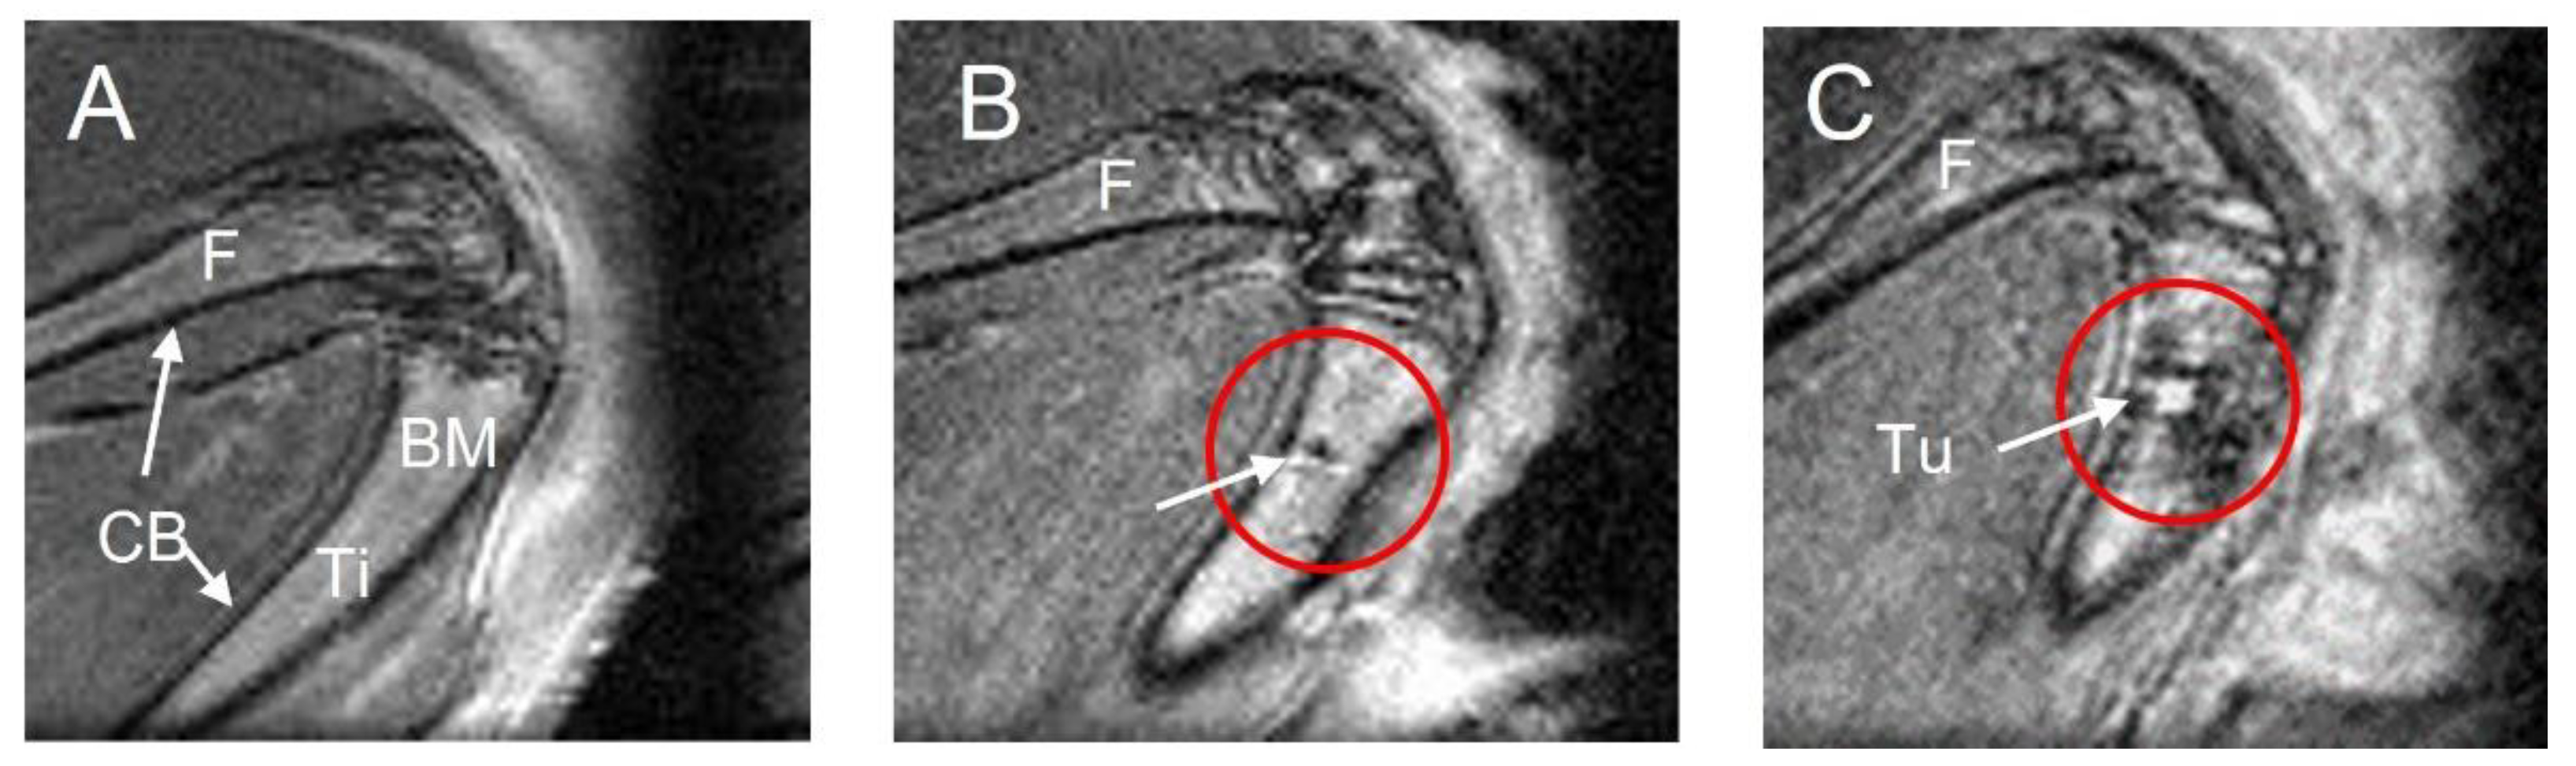

3.1. MRI Performance for Tumor Location and Phenotype Definition